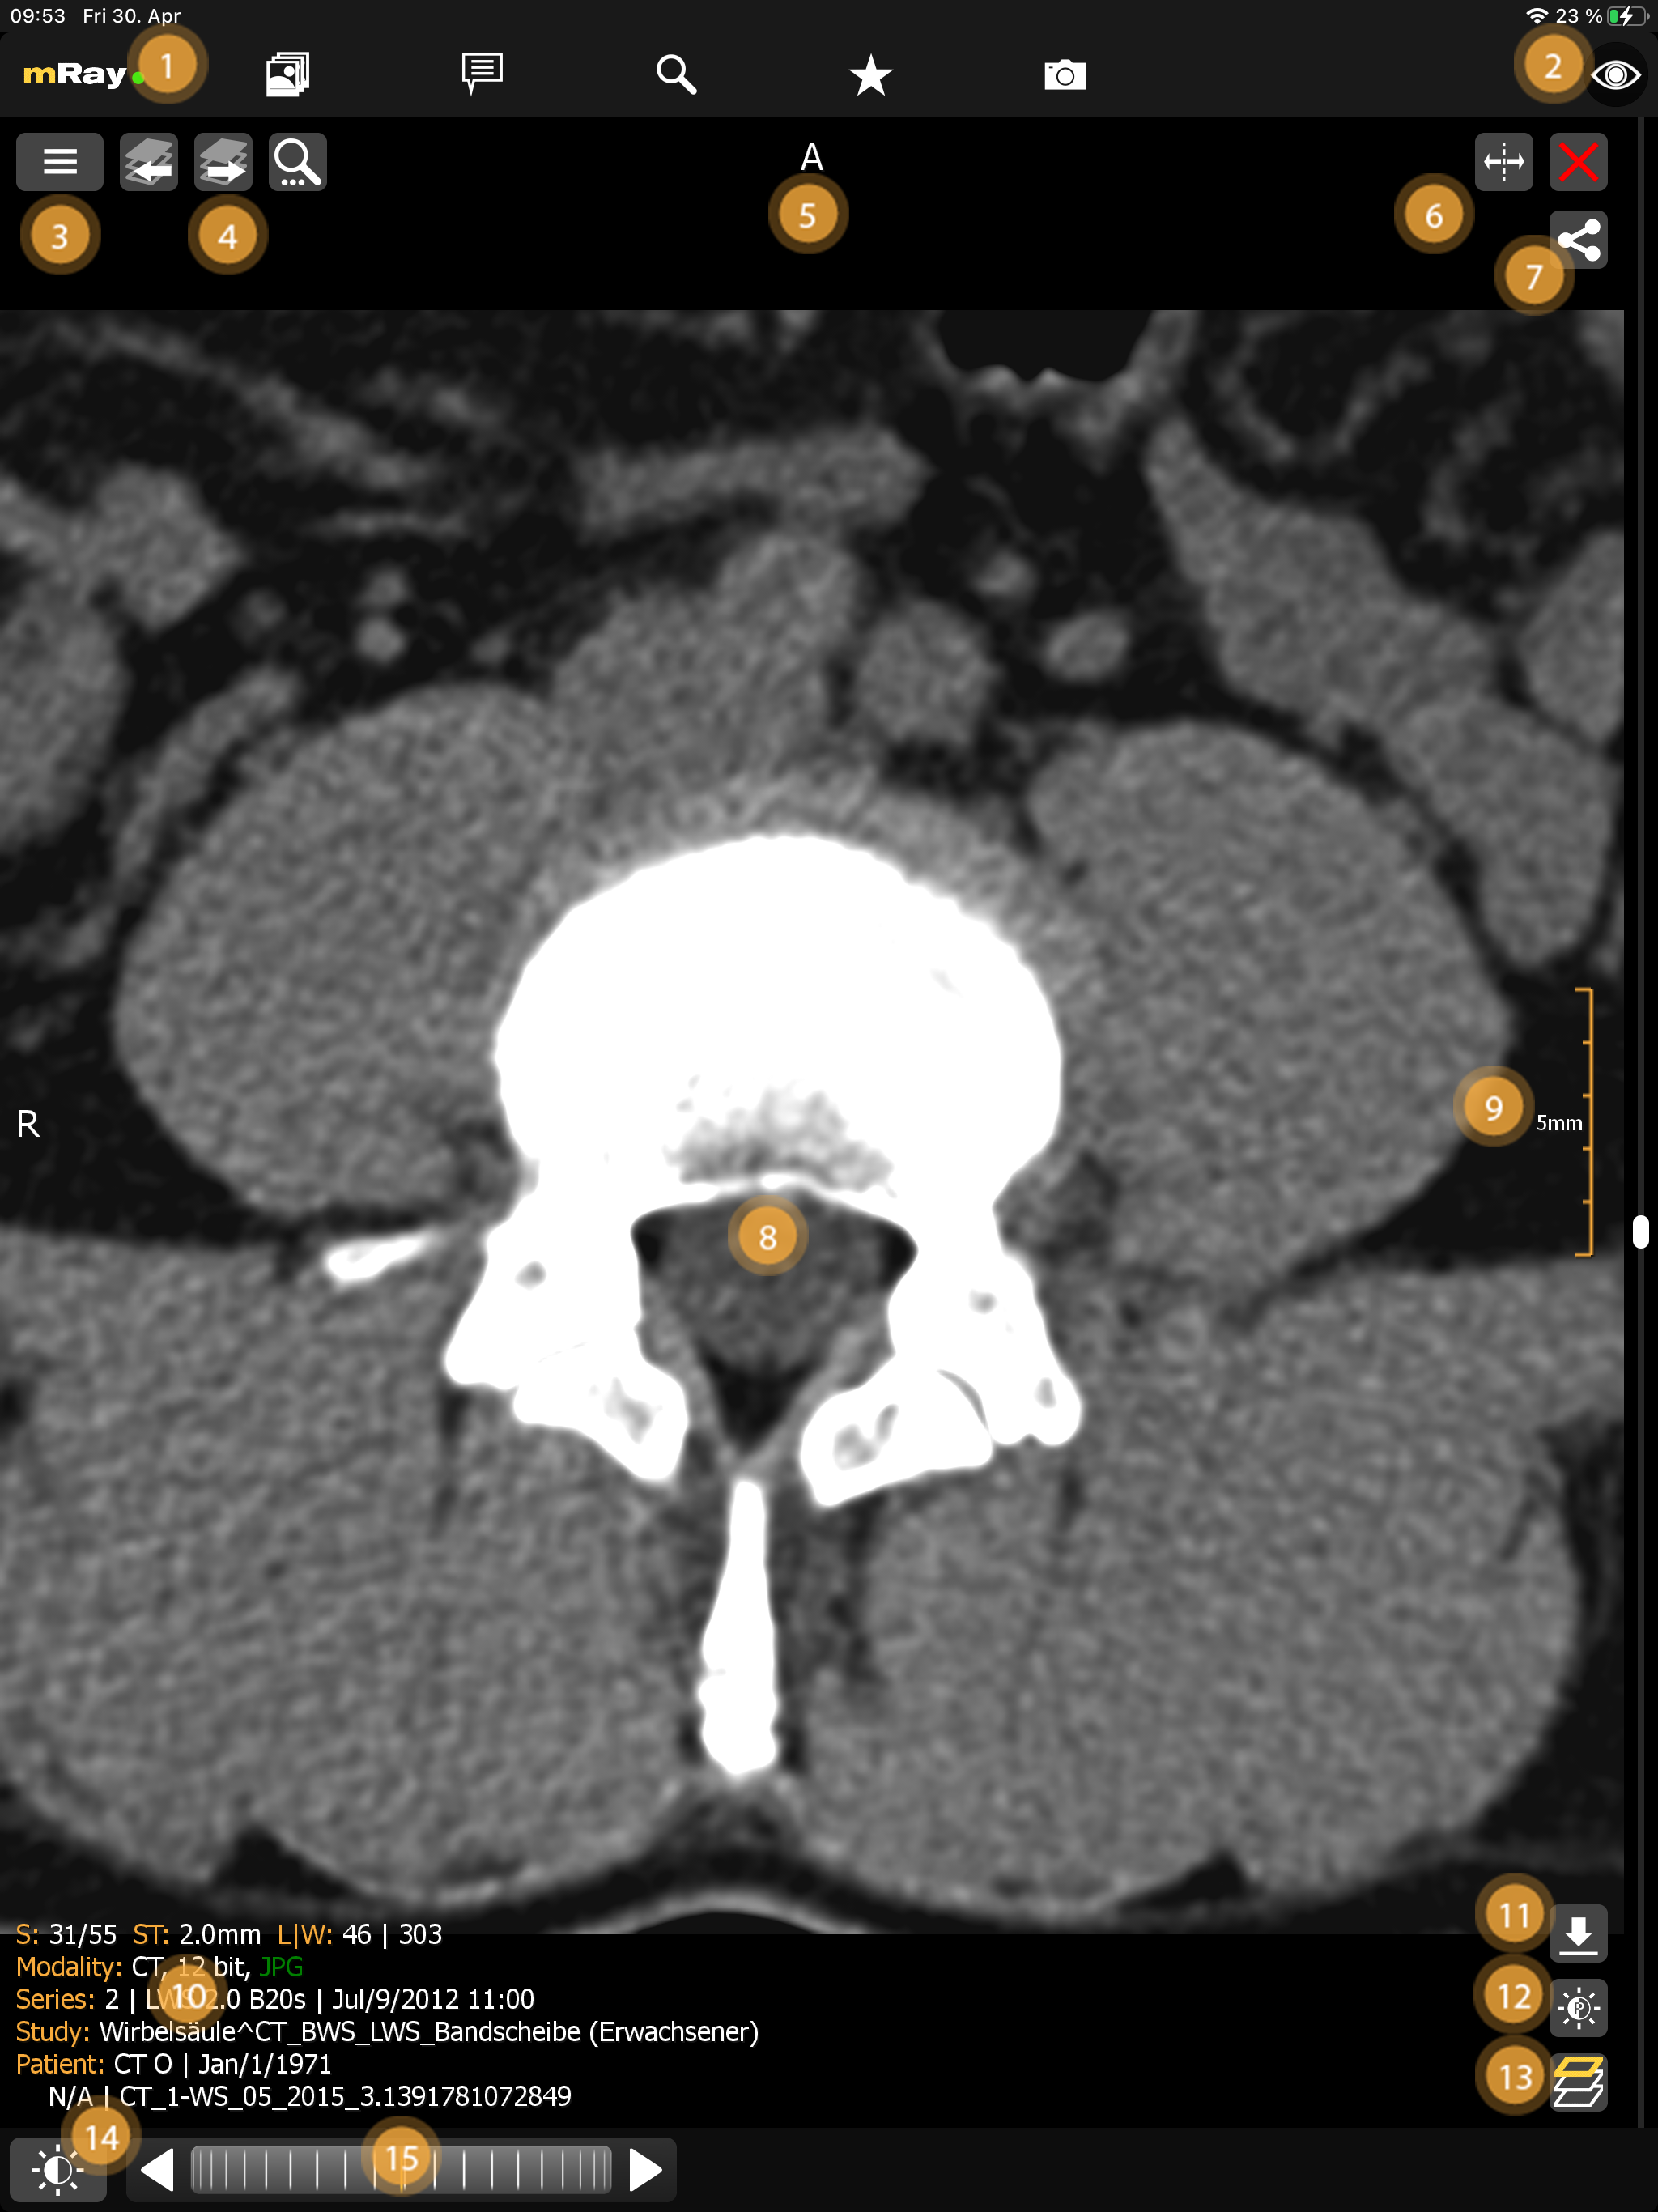

10. Viewer (Bildbetrachtung)

Nach Auswahl eines Datensatzes aus der Inbox öffnet sich der Viewer.

Folgende Funktionen stehen hier zur Verfügung:

-

Öffne das Hauptmenü und behalte die Verbindung zum Server über das Ampelsystem im Blick.

-

Toggle-Information-Button wechselt zwischen unterschiedlichen Modi für die Anzeige von Patienteninformationen:

-

Alle-Informationen: zeigt alle Bedienelemente und Informationen zum Datensatz an.

-

Minimale-Informationen: zeigt nur den Patientennamen und Bildorientierung an.

-

Keine-Informationen: nur die Bilddaten werden dargestellt.

-

-

Gehe zur Serienauswahl über diesen Button.

-

Wechsle zur vorherigen bzw. nächsten Serie, soweit mehr als eine Serie in der Studie vorhanden ist.

-

Zeigt, zusammen mit der komplementären Anzeige am linken Bildschirmrand, die Bildorientierung aus der Sicht des Patienten an. Dabei gibt es die folgenden Möglichkeiten (Kombinationen möglich):

-

R - Right: Die Richtung in der das X abnimmt.

-

L - Left: Die Richtung in der das X zunimmt.

-

A - Anterior: Die Richtung in der das Y abnimmt.

-

P - Posterior: Die Richtung in der das Y zunimmt.

-

I - Inferior: Die Richtung in der das Z abnimmt.

-

S - Superior: Die Richtung in der das Z zunimmt.

-

-

Der Split-Button teilt die aktuelle Ansicht, es wird ein weiteres Fenster geöffnet. Hinweis: Es gibt immer nur ein aktives Fenster. Dieses hat ein orange-gefärbten Rahmen. Durch Anklicken eines anderen Fensters aktivieren Sie dieses. Eine Interaktion findet nur im aktiven Fenster statt.

-

Schließen-Button schließt diese Ansicht.

-

Hier wird die Bilddatei angezeigt. Mit Hilfe der Tools (12) ist es möglich mit dem Bild zu interagieren. Solange der "FREE"-Modus eingestellt ist, ist es möglich mit zwei Fingern zu zoomen.

-

Die Maßanzeige gibt Aufschluss über die Skalierung des Bildes. Dabei ist zu beachten, dass die angegebene Länge stets die Innenlänge der Maßanzeige meint. Im obigen Screenshot beträgt die Gesamtlänge der Anzeige als 25 mm während jeder Zwischenschritt 5 mm lang ist.

-

Bilddatensatz-Informationen, z. B. Patient, Studie, Bildmodalität etc. Folgende Abkürzungen werden verwendet:

-

S: Die Schichtinformationen (aktuelle Schichtposition und Anzahl der Schichten)

-

ST: Die Schichtdicke

-

L|W: Die Level-Window Informationen

-

IN: Die DICOM Instance Number.

-

-

Download des aktuellen Datensatzes als DICOM-Daten (nur wenn vom Server unterstützt)

-

Level-Window auf Voreinstellungen setzen über den 'Level-Window'-Button.

-

MPR Perspektive Button zur Berechnung und Anzeige der unterschiedlichen Bildebenen. Hinweis: Diese Ebenen werden lokal auf dem Gerät errechnet. Siehe hierzu auch die Hinweise im Kapitel Bekannte Probleme.

-

Das Interaktionsmenü beinhaltet Werkzeuge für die Analyse der Bilddaten.

-

Das Scrollrad ermöglicht das Blättern durch die einzelnen Bildschichten, mit den links/rechts Pfeilen können Sie einzelne Schichten vor und zurück blättern (siehe Interaktionsleiste). Als weitere Option ermöglicht die Scrollbar, welche am rechten Bildschirmrand zu sehen ist, mit nur einem Finger durch die Bilder zu scrollen (siehe Scrollbar).